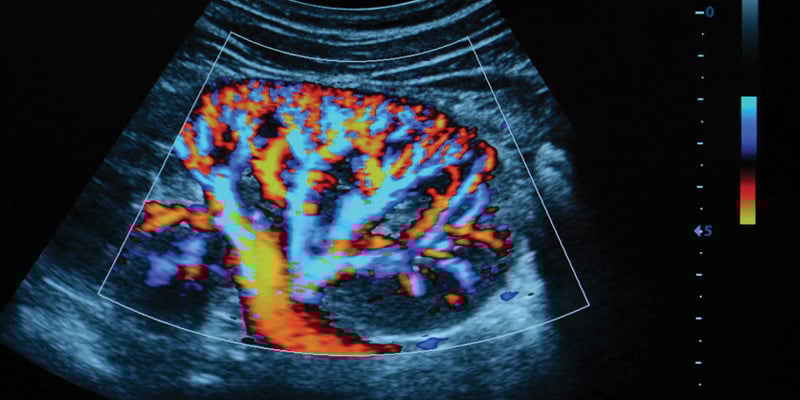

Sonography

Vascular Sonography